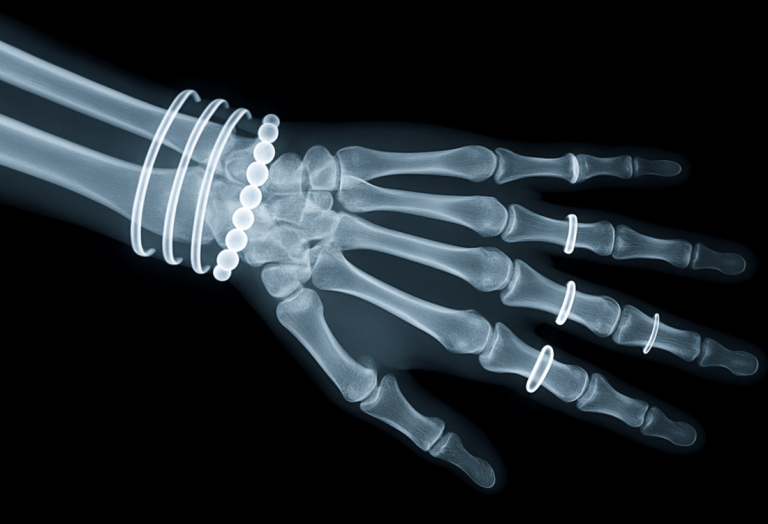

Natural Remedies for Treating Osteoporosis

Lifestyle changes help prevent fractures and protect bone density, which peaks in the 30s and...